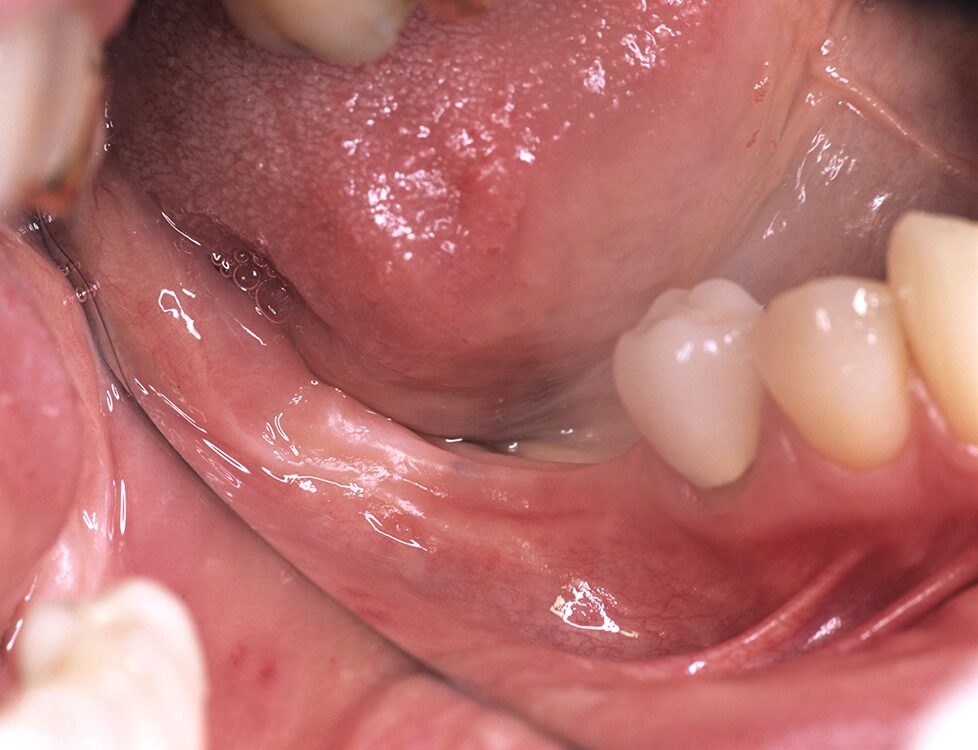

- Anatomie: Behandelte fortgeschrittene Parodontalerkrankungen sind klinisch stabil, zeigen aber in den implantatrelevanten anatomischen Knochenabschnitten (bukkale Lamellen, interapproximales Septum) weitere Abbauvorgänge durch Entzündung (Abb. 1 und 2) [1].

Daraus resultiert ein zweizeitiges Vorgehen mit (i) Entfernung prognostisch unsicherer Zähne, (ii) parodontaler Zieltherapie zur Sicherung des Restzahnbestandes, ergänzt durch (iii) mikrochirurgische Revision tiefer Resttaschen vor Implantation zum weiteren Entzündungsschutz (Abb. 3 und 4). Die Implantatplanung bleibt vorläufig. Ein definitiver Kostenvoranschlag wird erst nach funktioneller Entlastung und digitaler Beurteilung der Implantatknochenanatomie erstellt.